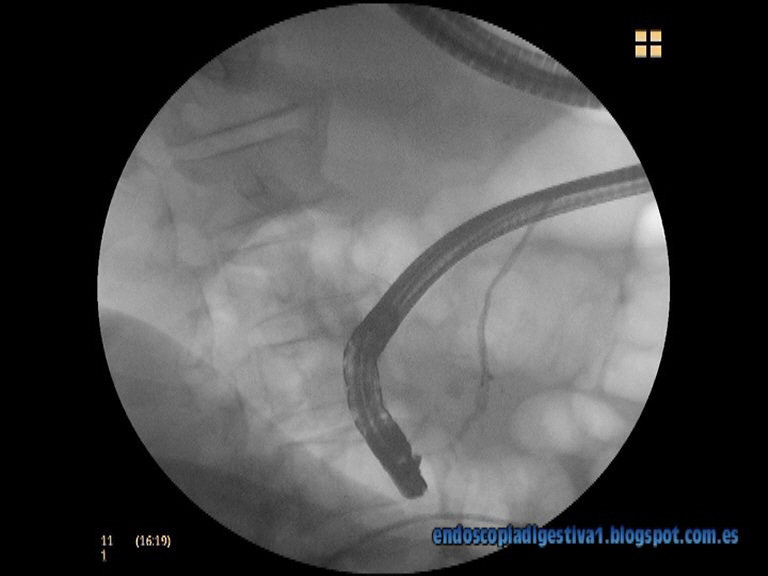

Paciente varón de 81 años de edad, con antecedentes de cardiopatía isquémica (IAM en 2004) con cateterismo y colocación de 2 stents coronarios HTA e ICC asociada. Ingresa por un cuadro clínico y analítico compatible con pancreatitis aguda biliar, aunque en la geografía no se apreció litiasis biliar (BRT 3 mgr/dl con predominio de la fracción directa, GPT 136 UI/L, amilasa de 1421 UI/L). La evolución en las siguientes 48 horas fue tórpida y aplicando el protocolo de valoración de la gravedad de la PA del Club Español Pancreático que considera PA grave si aparecen mas de 2 valoraciones positivas (primeras 24 horas: impresión clínica de gravedad APACHE-II > 8; a las 48 h: Ranson > 3, PCR > 150 mgr/dl; al 4º día: TAC dinámico con contraste y aparición de fracaso orgánico (FO) en cualquier momento). La pancreatitis se consideró por tanto de gravedad. Como datos destacables de lo referido, en las primeras 24 horas, el paciente presentaba sensación de enfermedad grave, con dolor abdominal intenso, importante distensión abdominal, signos de deshidratación, TA 90/60 mm Hg y una valoración APACHE-II > 12. A las 48 horas del ingreso la puntuación Ranson era de 4 puntos, destacando un Hto del 45 %, urea 104, creatinina 1.3, calcio 7.9, plaquetas 81000 con AP del 63 % y PCR de 27 mgr/dl. En la placa de tórax destacaba un derrame pleural bilateral importante asociado a cardiomegalia. En el TAC realizado se aplicó un valor C de Balthazar sin necrosis. En este momento se consultó con la UCI que desestimó el ingreso en dicha ubicación por el pobre pronóstico y la edad del paciente. En este momento, a la desesperada, se decide realizar CPRE urgente para intentar una esfinterotomía biliar. En la intervención destaca un importante edema de los pliegues duodenales a nivel del área papilar. La papila es de difícil localización y posicionamiento al encontrarse en el margen izquierdo de un divertículo. La conjunción del edema de pliegues, el divertículo yuxtapapilar y el peristaltismo, tras 45 minutos de intervención, hacen imposible la canulación biliar. Ante este evento, se decide usar un canulotomo para poder entrar en Wirsung, que finalmente se consigue. Se realiza pancreatografía confirmatoria y se decide colocar un stent pancreático de 5 Fr/5 cm con flaps duodenal e interno con muy buen drenaje del contraste.

Y ahora el video: